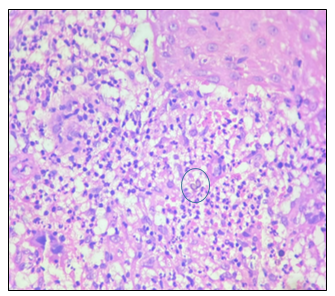

Histopathological examination revealed pseudoepitheliomatous hyperplasia, suppurative granuloma with epithelioid cells, multinucleated Langhans giant cells, lymphohistiocytic infiltrate, and the presence of sclerotic (Medlar) bodies on hematoxylin and eosin staining.

The patient was initiated on oral Itraconazole 200 mg daily, with liver function tests monitored biweekly. Marked clinical improvement was observed after three months of treatment.

(Figure 11– Figure 14)

Figure 12 Histopathological features showing pseudoepitheliomatous hyperplasia and suppurative granulomas with Medlar bodies

Figure 13 Medlar bodies on HPE